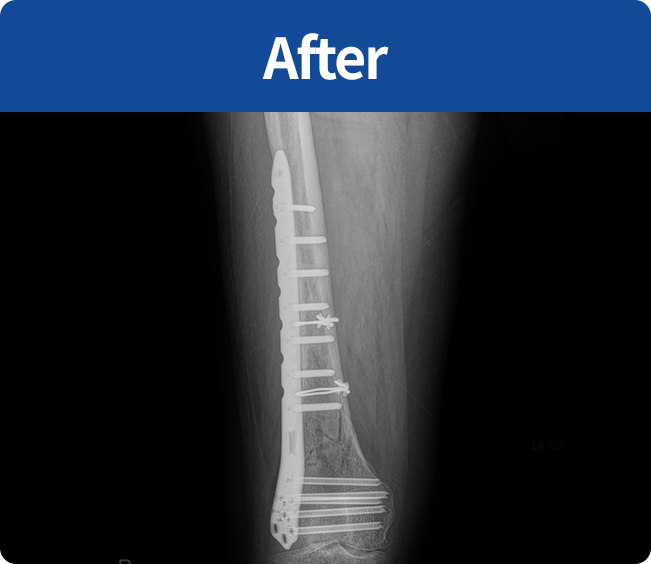

골절 고정술

부러진 뼈를 해부학적 위치로 정확하게 맞춘 뒤,

뼈가 안정적으로 붙을 수 있도록 금속판, 나사, 핀 등을 이용해 고정하는 수술

(내고정술, 외고정술)